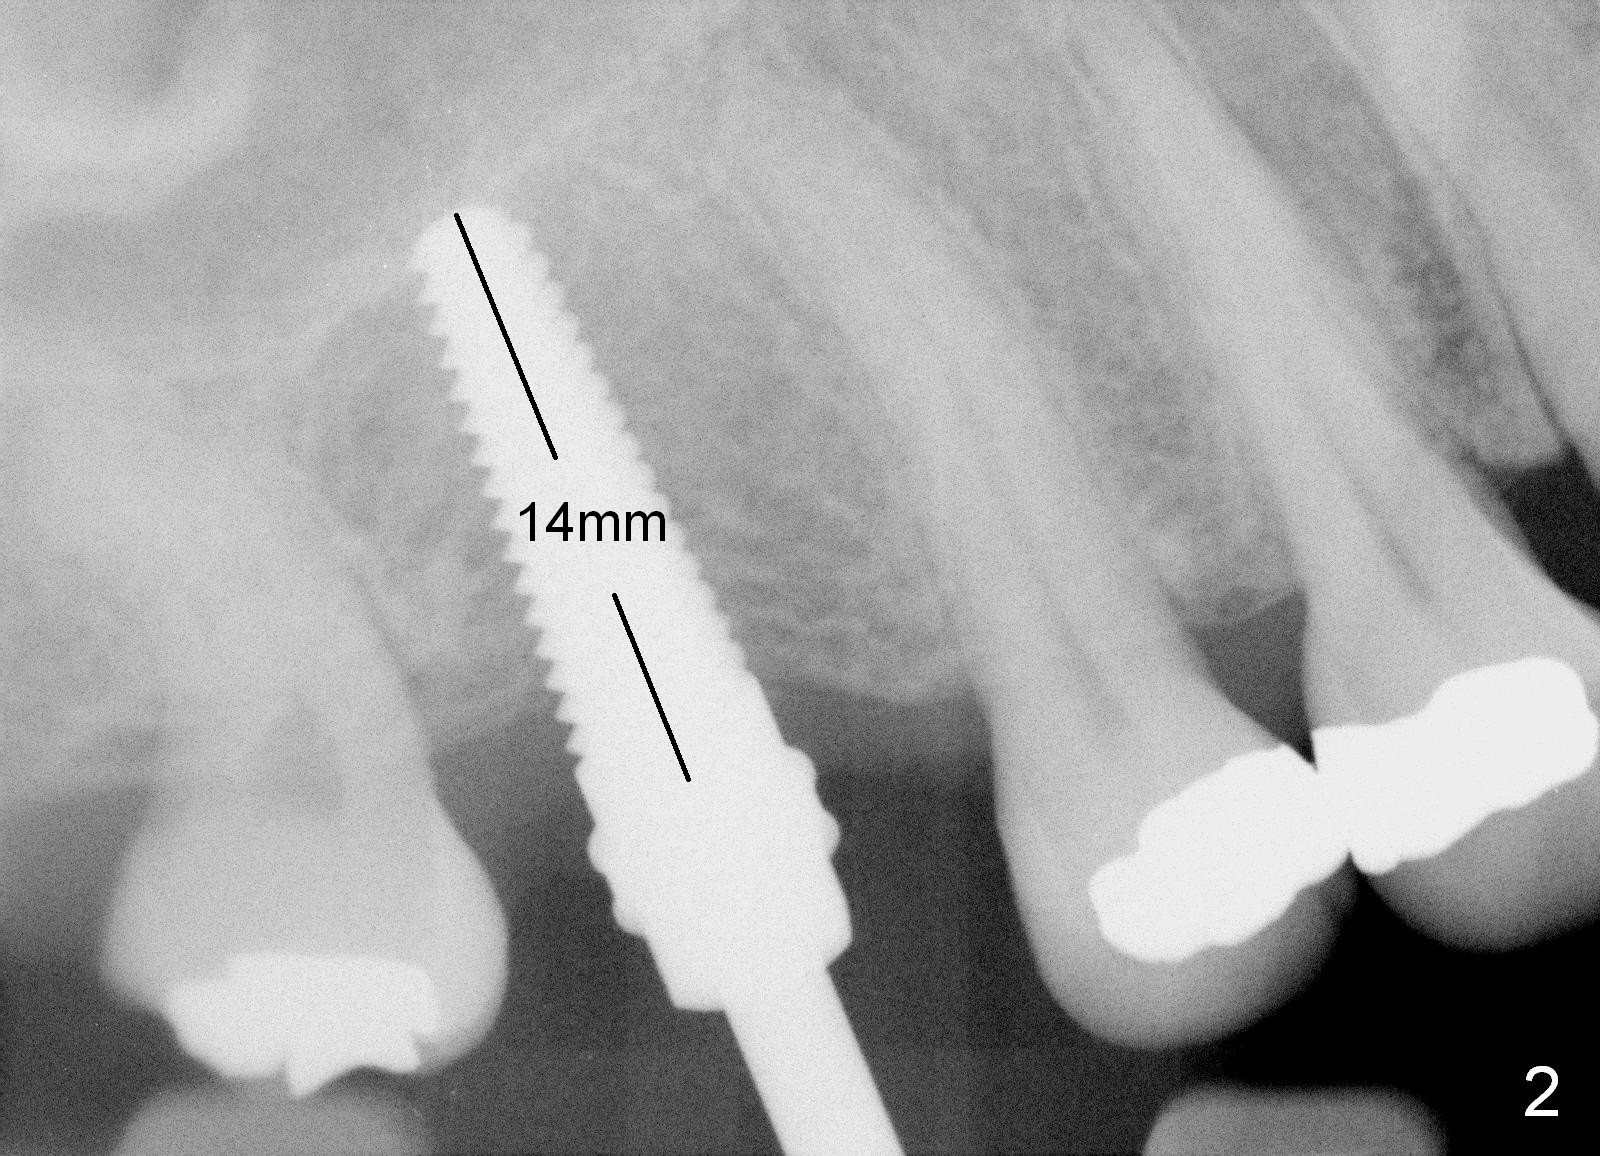

A 50-year-old lady requests implant placement at the site of #3 first. The ridge is mild to moderate atrophy. Immediately preop PA shows bone height ~ 10 mm (Fig.1 green line) and gingiva to sinus floor distance 12 mm (red line). A 10 mm incision is made over the crest. The bone is felt D3, whereas the earlier case D4. Bone expansion and condensation is still performed because it is the least invasive, no drill or suture. In brief the osteotomy is created by osteotomes, followed by taps (4.5-6 mm) (Fig.2: 4.5 mm). A 6x14 mm gingiva-level implant is placed with insertion torque of 60 Ncm (Fig.3 I). A 5x3 mm abutment (A) is placed for an immediate provisional. There is no bone resorption less than 4 months postop (Fig.4). After reprep, impression is taken for final restoration.